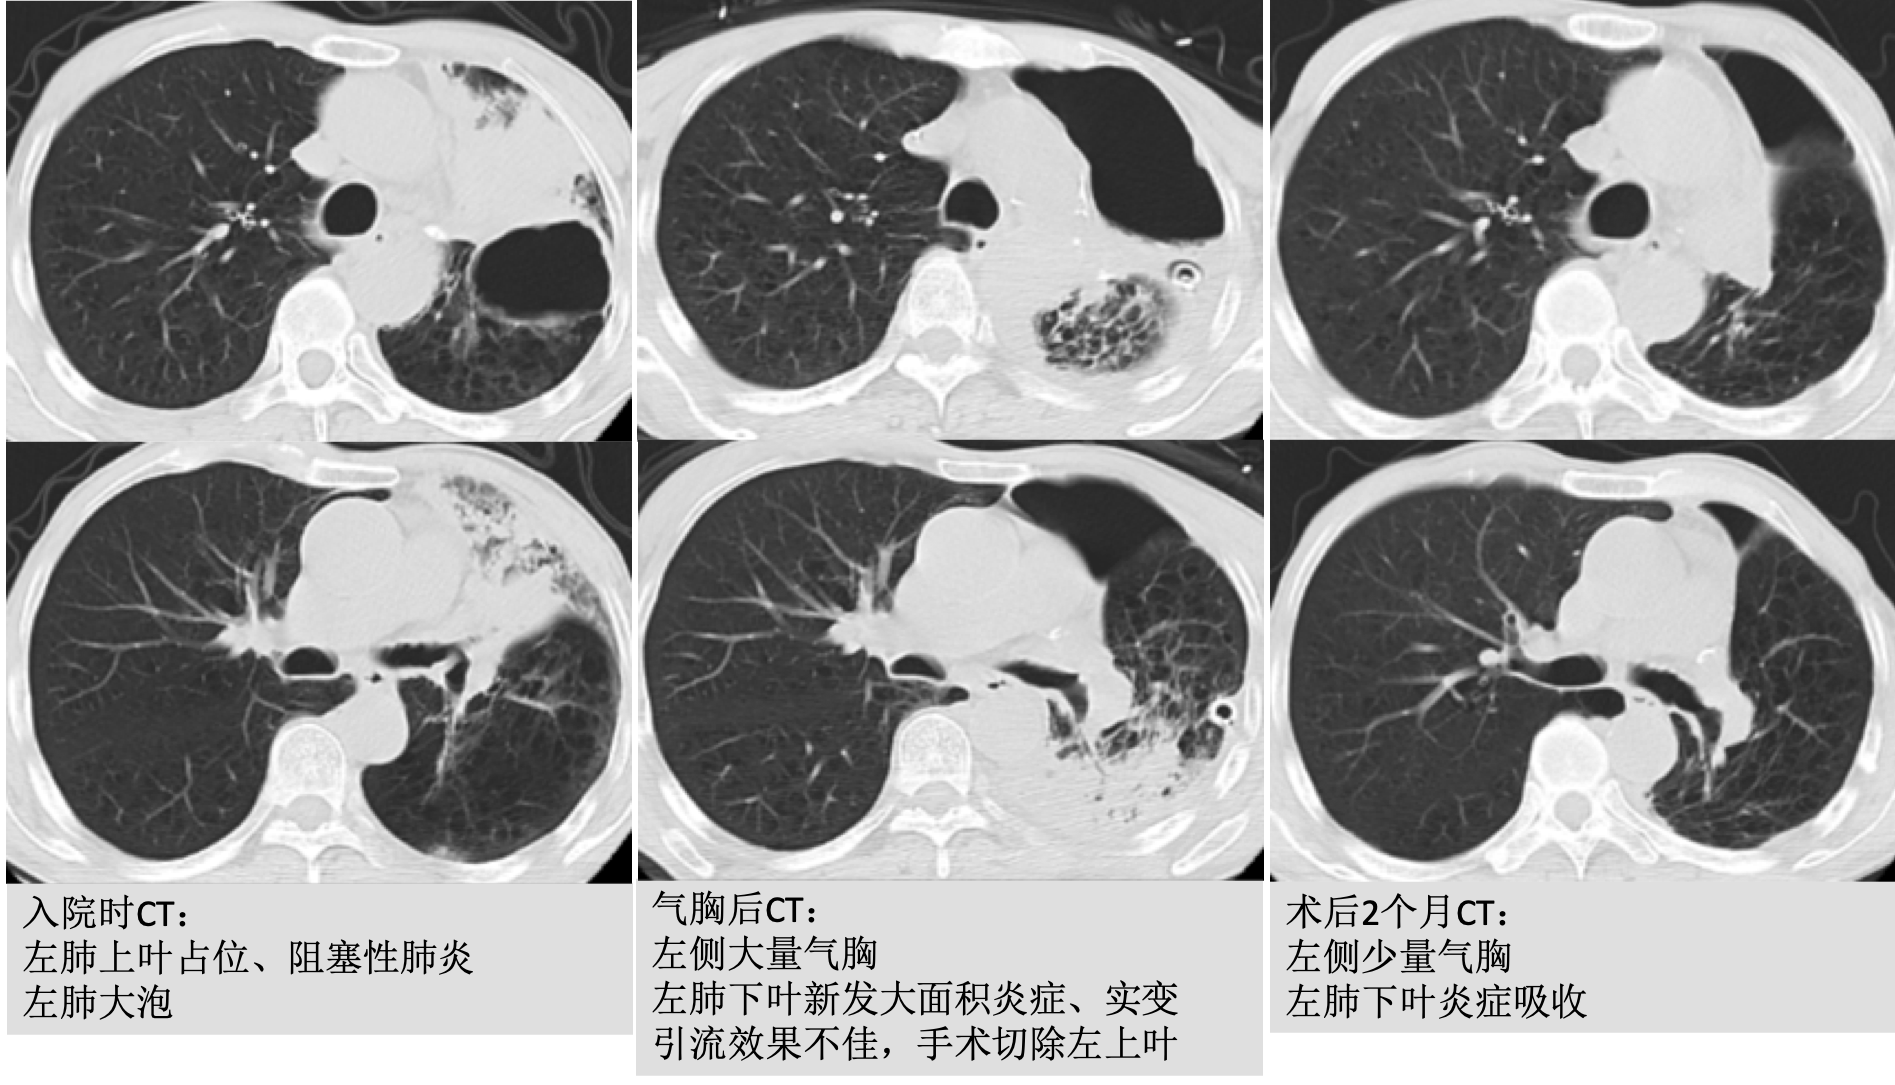

点评1,这是一例肺癌继发肺大泡,肺大泡破裂引起气胸的患者,由于患者